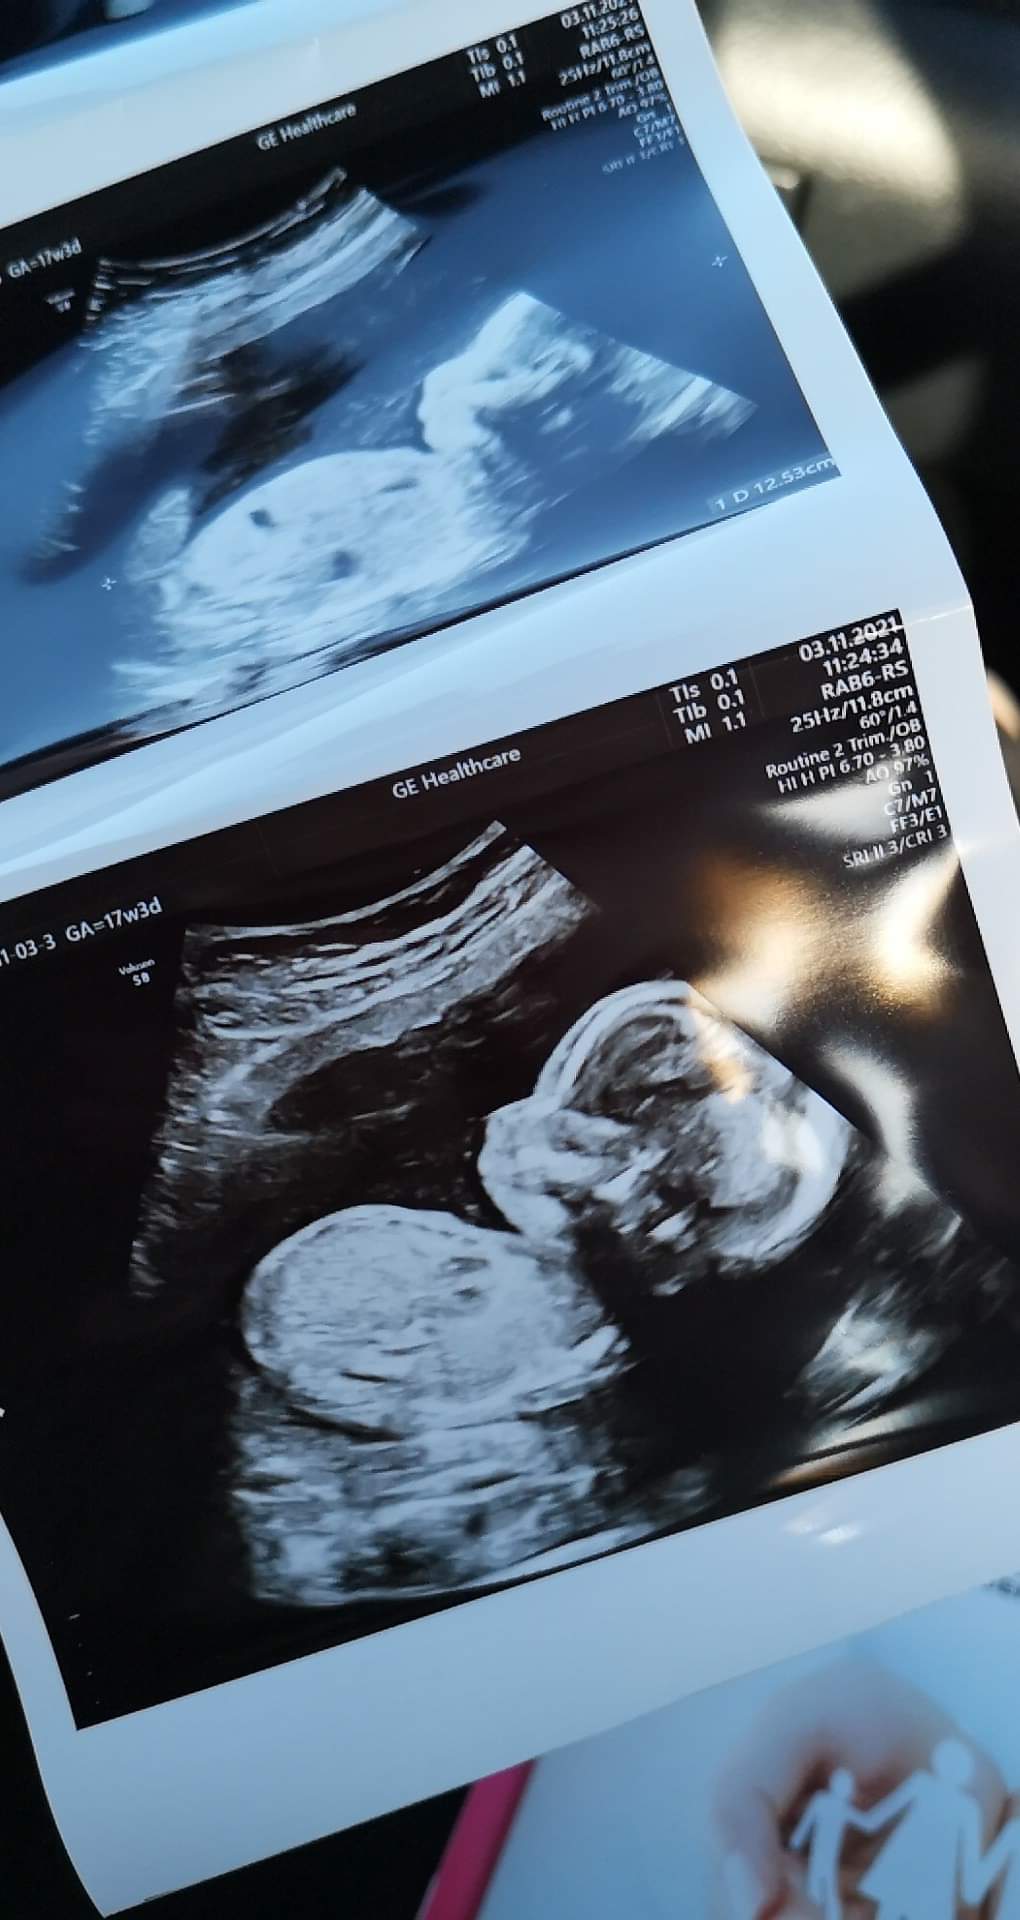

A więc na wizycie super bo zobaczyłam naszego synusia i tatuś też, wszystko jest okej i 2 grudnia mamy połówkowe 😊 niestety doszła mi anemia.. Aż nie mogłam uwierzyć, że ja.. Nigdy nie miałam problemu z żelazem bo zawsze było bardzo ładne bo zawsze w okolicy 120 😁 a teraz mówią, że mam anemię bo hemoglobina niska... 😐 Dostałam rozpiske jak jeść i zobaczymy za miesiąc jaki będzie wynik 🙄 dzidziuś wyciąga ze mnie wszystkie witaminki 🙈 odrazu były pytania czy nie chodzę jakaś zmęczona i czy męczę się szybciej.. Myślam, że to poprostu objawy ciąży 😁 ważne, że z dzidziusie wszystko okej ❤️ przepraszam jeśli tak bez ładu i składu ale 😅 dzidziuś wyprostowany ma 20 cm, i był dzisiaj bardzo ruchliwy i pani doktor miała gimnastykę, serio musiałbyście widzieć to uzg 😂

A tu zdj ❤️